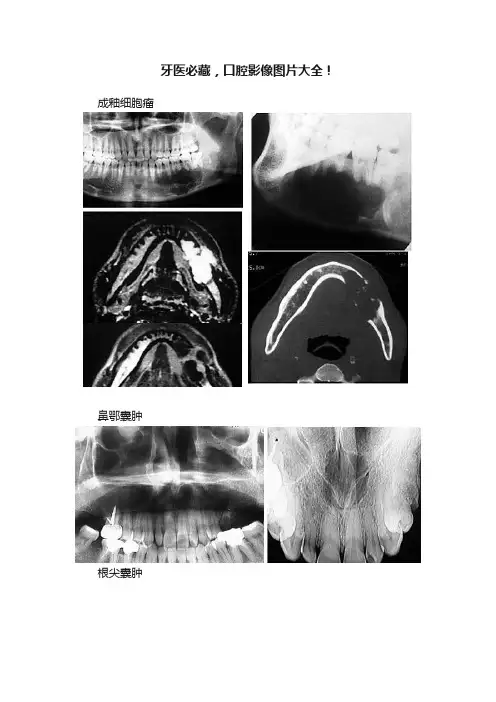

牙医必藏,口腔影像图片大全!成釉细胞瘤

鼻鄂囊肿

根尖囊肿